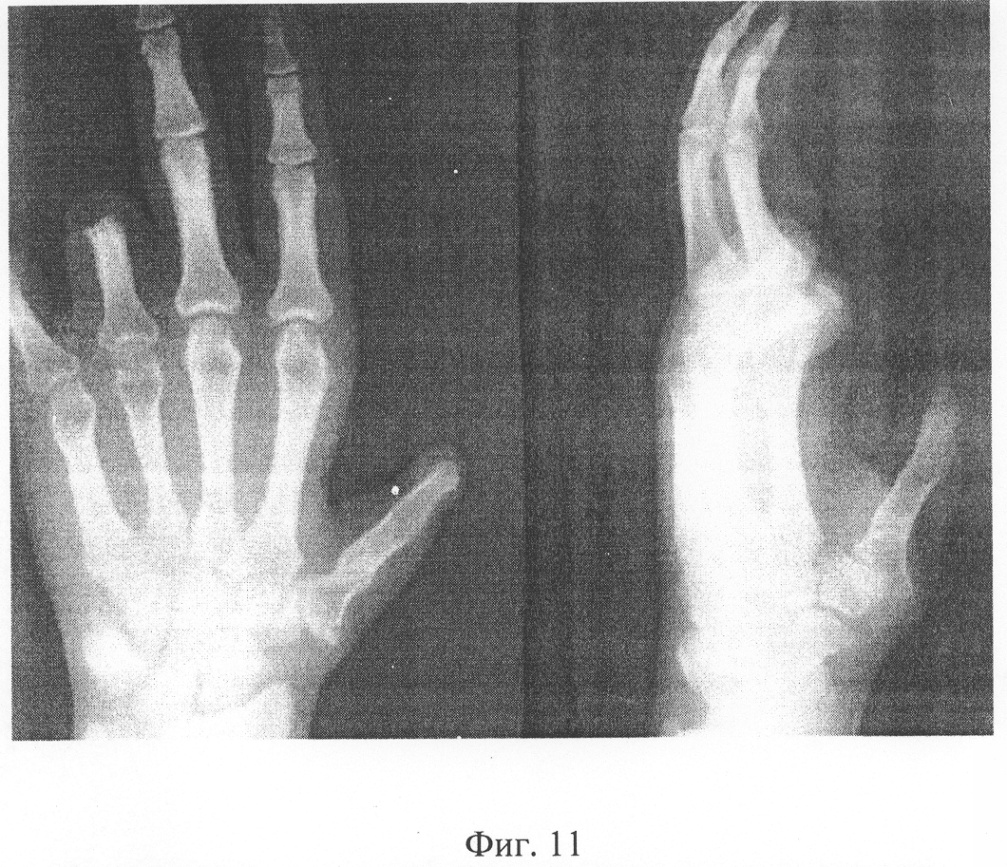

Б-ой С., 1976 г.р. И.Б. №1648, поступил в отделение хирургии кисти НИЦТ “ВТО” 19.04.02. Диагноз: Культя 1 пальца на уровне основания пястной кости, культи основных фаланг 4-5 пальцев левой кисти (Фиг.1, 2, 3,4).

Осмотрен на сроке 1 год после операции. Функция сформированного 1 пальца левой кисти хорошая, трофических нарушений нет. Результатом операции пациент доволен (Фиг.11, 12, 13, 14).